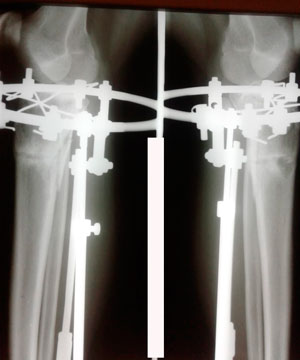

на пути к ровным ножкам!

Вложения

IMG_6685-25-10-19-11-12.JPG